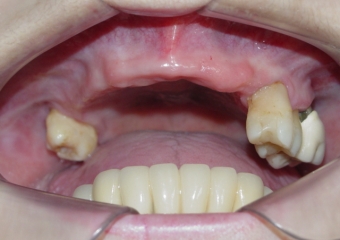

Imagens iniciais